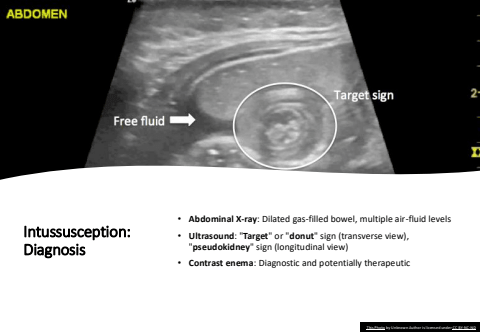

Intussusception: Diagnosis%u2022 Abdominal X-ray: Dilated gas-filled bowel, multiple air-fluid levels%u2022 Ultrasound: \\ sign (longitudinal view)%u2022 Contrast enema: Diagnostic and potentially therapeuticThis Photo by Unknown Author is licensed under CC BY-NC-ND